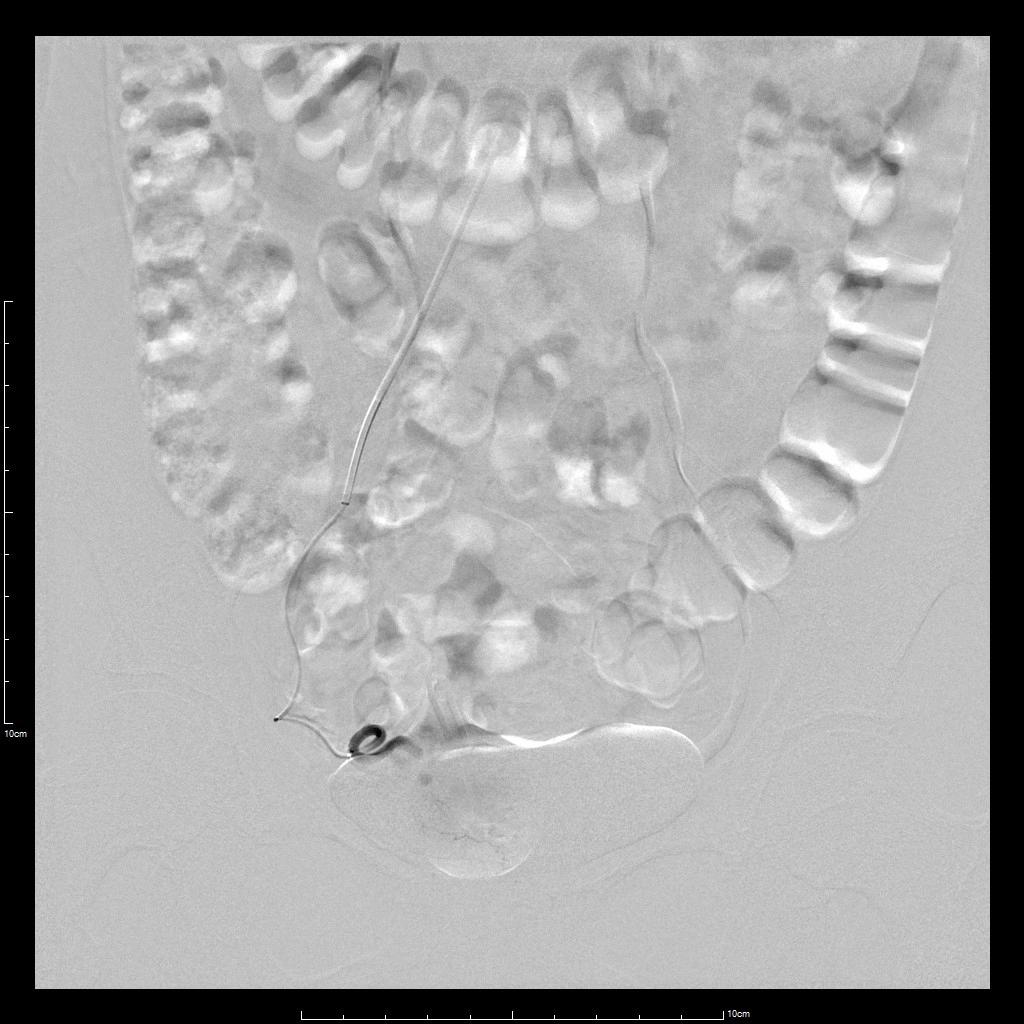

- 超选择插管右侧子宫动脉病灶供血动脉造影+栓塞治疗。